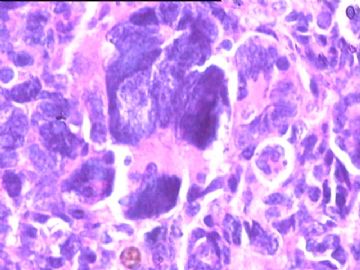

女,34y,头痛一月,右额叶占位:5*5*4cm。囊性区域,4cm。大体:3.5x3x1cm灰白间暗褐色组织一堆,质嫩。临床诊断1:胶质瘤,2:血管母细胞瘤。

本人县级医院头颅手术少,考虑胶质母细胞瘤。大家指导指导。

同意胶质母细胞瘤。细胞异型、坏死、核分裂、血管内皮肿胀增生均可见到。

This is certainly a WHO grade IV malignant neoplasm. While most likely a glioblastoma, I would carefully rule out PNET by staining for GFAP and neuronal markers such as synaptophysin, NeuN and NSE. Rarely, PNET may shows marked pleomorphism and indistinguishable from glioblastoma on HE stain.

同意马老师的意见,该肿瘤从形态及年龄来看考虑PNET或GBM,须标记Syn、NSE、S-100、NeuN和GFAP来鉴别。

结合图片细胞形态特点考虑胶质母细胞瘤,组化标记排除其他